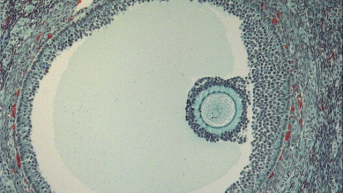

O teste de ovulação basicamente detecta um hormônio em abundância que faz o folículo romper e o óvulo sair para as trompas. O LH, hormônio luteinizante, em seus picos são capturados pelos anticorpos e reagentes existentes na tira de teste e fazem com que a linha de teste fique mais escura ou da mesma cor que a linha de controle. Caso a linha fique clara, então é sinal que o pico hormonal ainda não ocorreu.